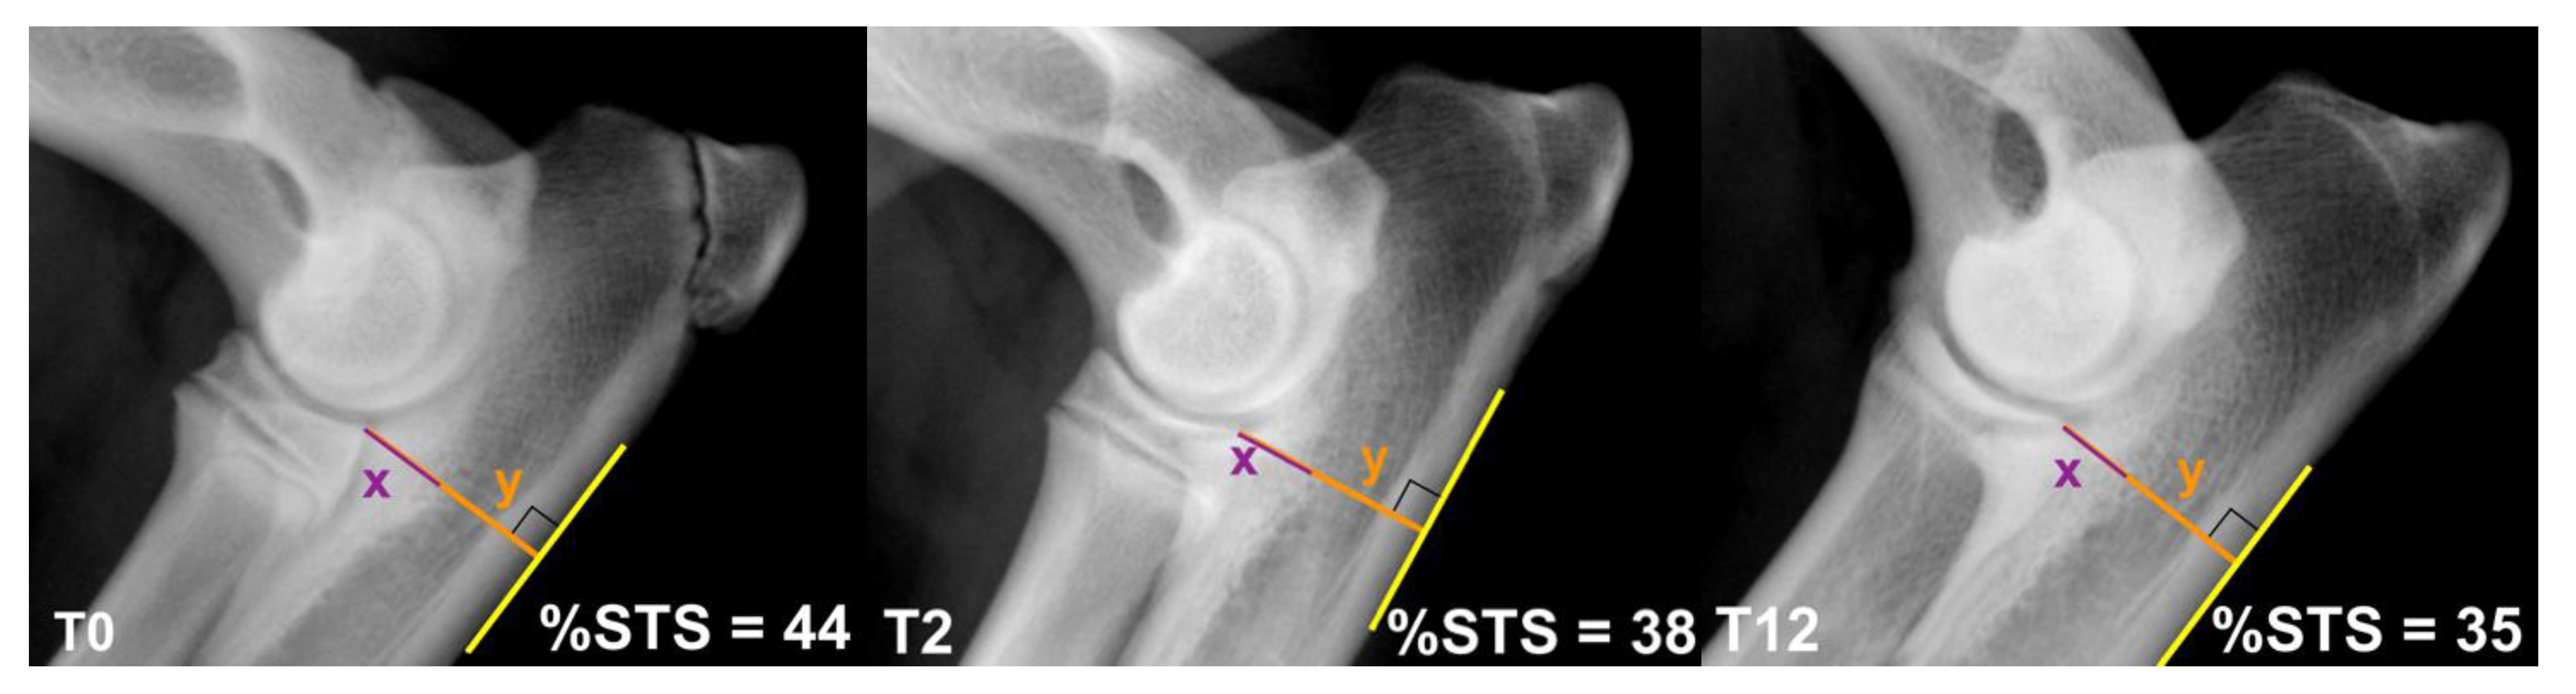

- Smith, T.J.; Fitzpatrick, N.; Evans, R.B.; Pead, M.J. Measurement of ulnar subtrochlear sclerosis using a percentage scale in Labrador Retrievers with minimal radiographic signs of periarticular osteophytosis. Vet. Surg. 2009, 38, 199–208. [Google Scholar] [CrossRef] [PubMed]

| % STS | T0 | 47.3 ± 7.2 | 46.3 ± 7.6 | 42.5 ± 9.6 | 1.213 | .3077 | DUO vs. BODPUO | .7182 | 47.2 ± 8.2 | 1.297 | .2857 | DUO vs. BODPUO-ND | .9843 | 44.0 ± 6.2 | .7881 | .4429 |

| DUO vs. CM | .3595 | DUO vs. CM | .3855 | |||||||||||||

| CM vs. BODPUO | .4154 | CM vs. BODPUO-ND | .3855 | |||||||||||||

| T2 | 42.6 ± 5.3 | 49.3 ± 15.4 | 45.1 ± 11.8 | 1.384 | .2620 | DUO vs. BODPUO | .2880 | 46.0 ± 9.7 | .5655 | .5730 | DUO vs. BODPUO-ND | .6844 | 57.2 ± 24.2 | 1.402 | .1812 | |

| DUO vs. CM | .5902 | DUO vs. CM | .7228 | |||||||||||||

| CM vs. BODPUO | .5902 | CM vs. BODPUO-ND | .8083 | |||||||||||||

| T12 | 40.4 ± 5.0 | 43.8 ± 9.4 | 52.4 ± 14.9 | 4.868 | .0127 | DUO vs. BODPUO | .3396 | 41.4 ± 9.1 | 5.381 | .0090 | DUO vs. BODPUO-ND | .7969 | 49.4 ± 8.1 | 1.692 | .1112 | |

| DUO vs. CM | .0110 | DUO vs. CM | .0118 | |||||||||||||

| CM vs. BODPUO | .0592 | CM vs. BODPUO-ND | .0235 | |||||||||||||

| T24 | 41.0 ± 6.0 | 44.5 ± 9.8 | 58.3 ± 22.3 | 6.047 | .0050 | DUO vs. BODPUO | .4514 | 41.5 ± 9.2 | 6.427 | .0041 | DUO vs. BODPUO-ND | .9226 | 51.6 ± 7.8 | 2.152 | .0481 | |

| DUO vs. CM | .0050 | DUO vs. CM | .0066 | |||||||||||||

| CM vs. BODPUO | .0189 | CM vs. BODPUO-ND | .0096 | |||||||||||||

| χ2r | 6.348 | 1.347 | 13.20 | 3.848 | .7864 | |||||||||||

| p-Value | .0108 | .2740 | .0025 | .0483 | .4487 | |||||||||||